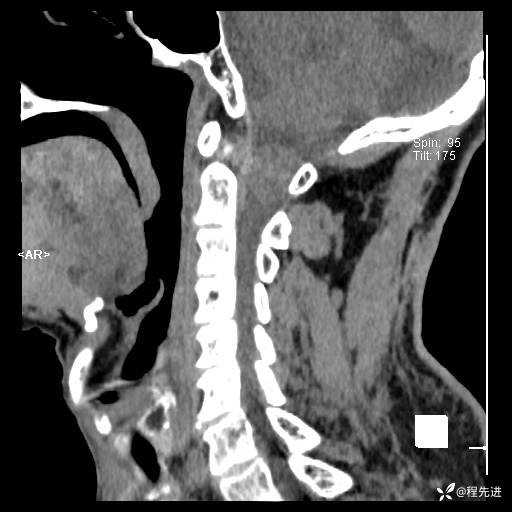

CT平扫: